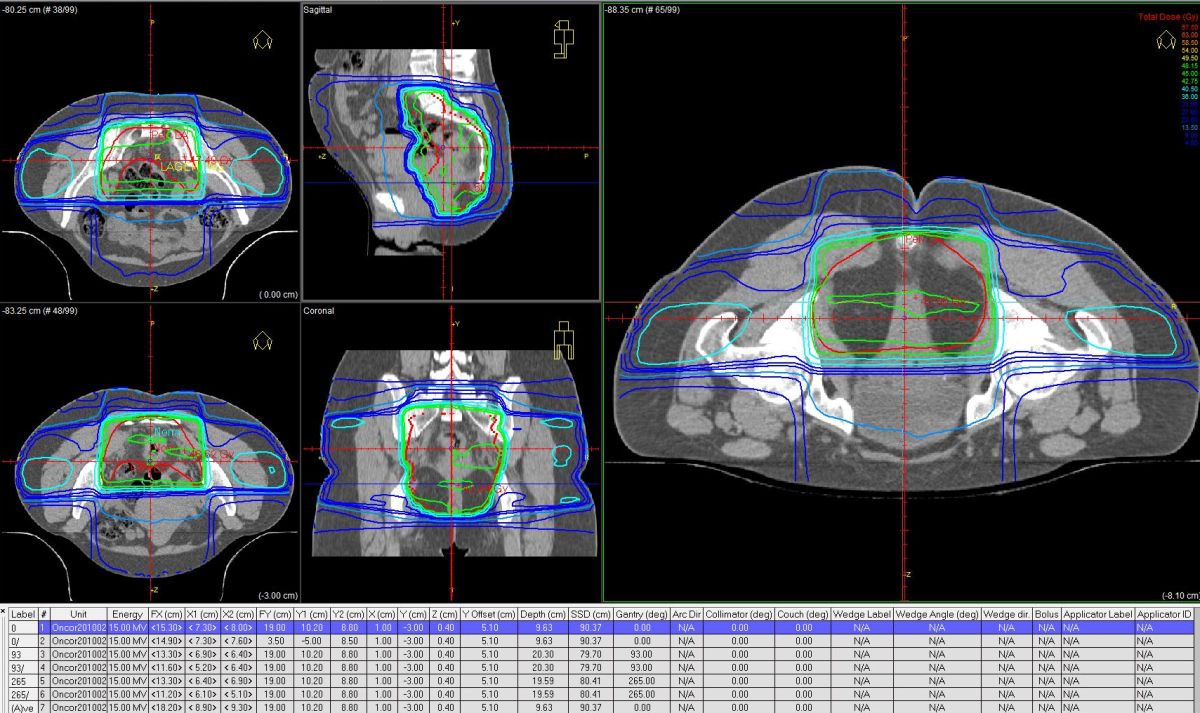

IMRT |

IMRT erlaubt eine bessere Schonung von Blase und Darm. | IMRT in Bauchlage ermöglicht eine geringere Dünndarmdosis als IMRT in Rückenlage. | |||